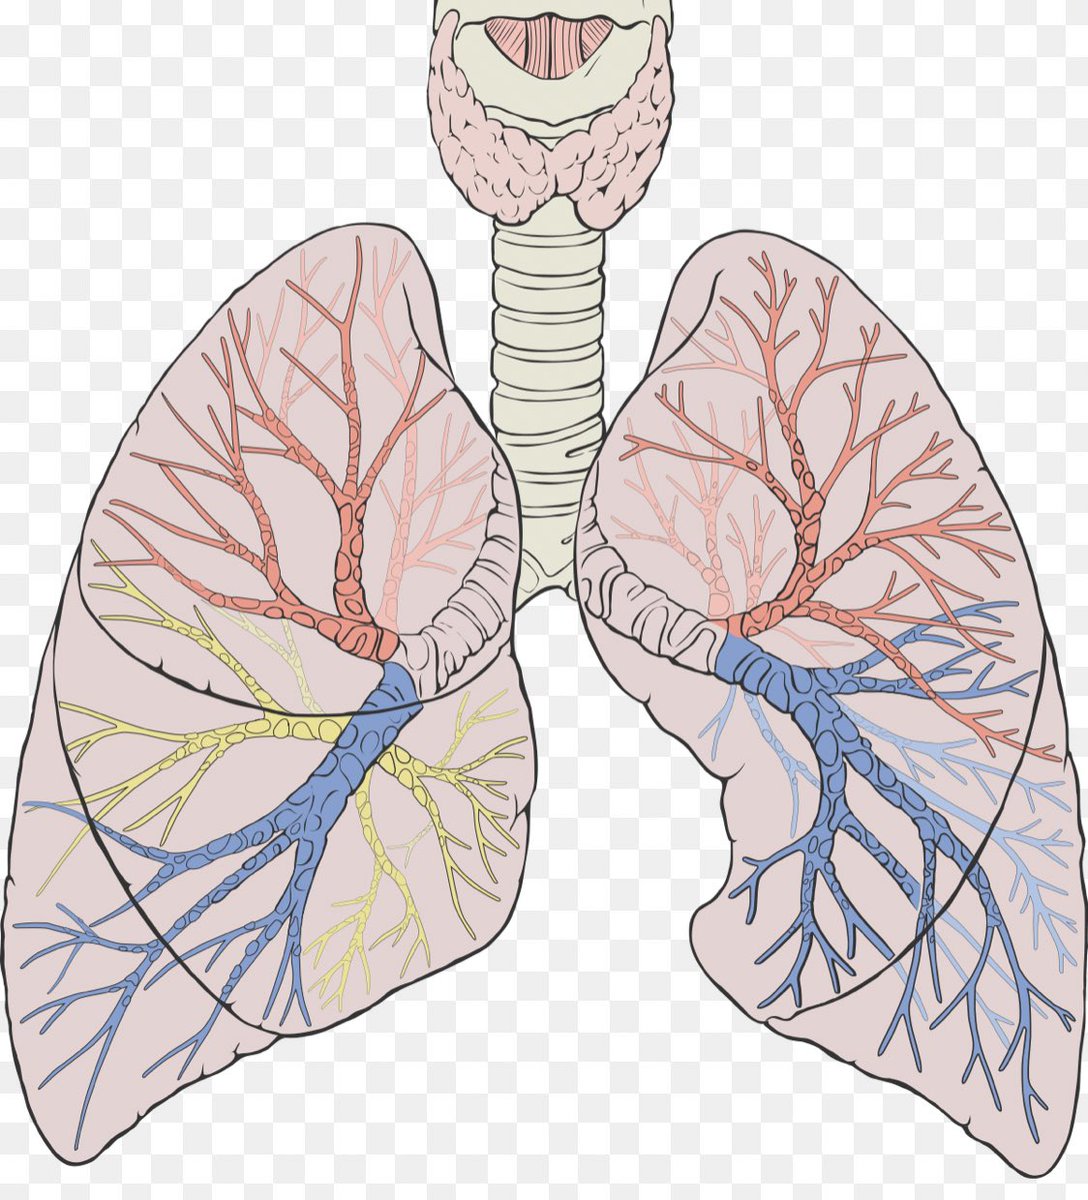

تنقسم الرئة لجزء أيمن يُقسم بدوره إلى فصين وأيسر يُقسم إلى ثلاثة فصوص ، كوفيد غالباً يبدأ التهابه من "الأطراف/الأضلاع" في الفصوص السفلية من الرئة وغالباً في الجهتين